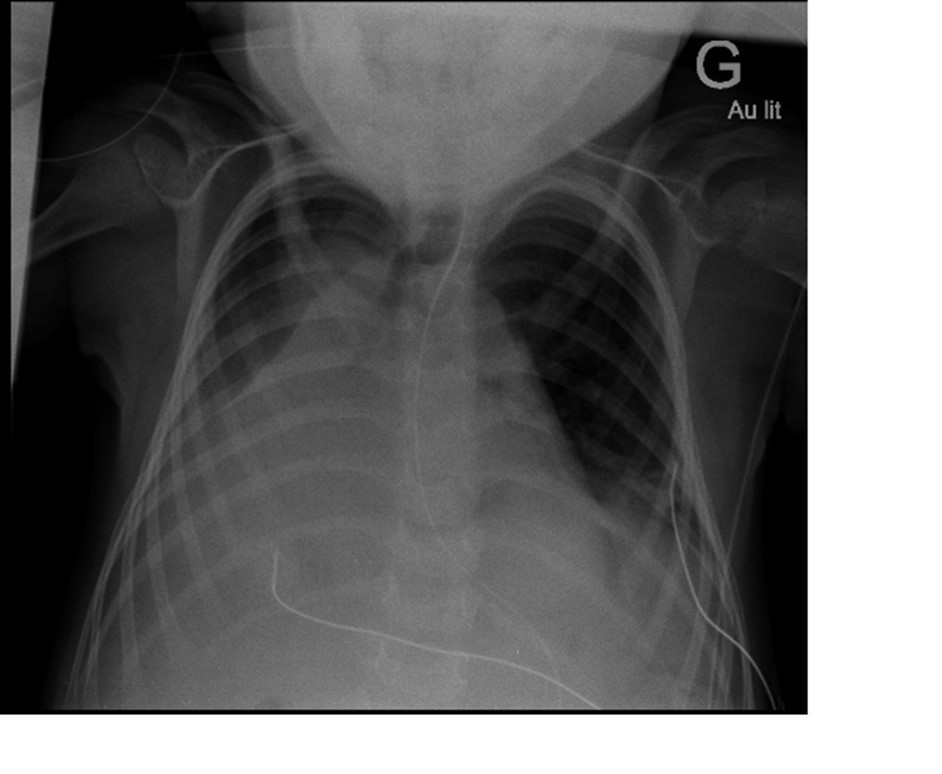

Radiographie de thorax :

Question 14 : Vous prenez la ou les mesure(s) diagnostique(s) et thérapeutique(s) suivantes.

L’hypercapnie impose une aide ventilatoire de type ventilation non invasive dans un premier temps

Les troubles de la déglutition et l’intensité de la détresse respiratoire imposent l’arrêt de l’alimentation orale

La ponction pleurale aura un double objectif : diagnostique (culture bactérienne) et évacuatrice